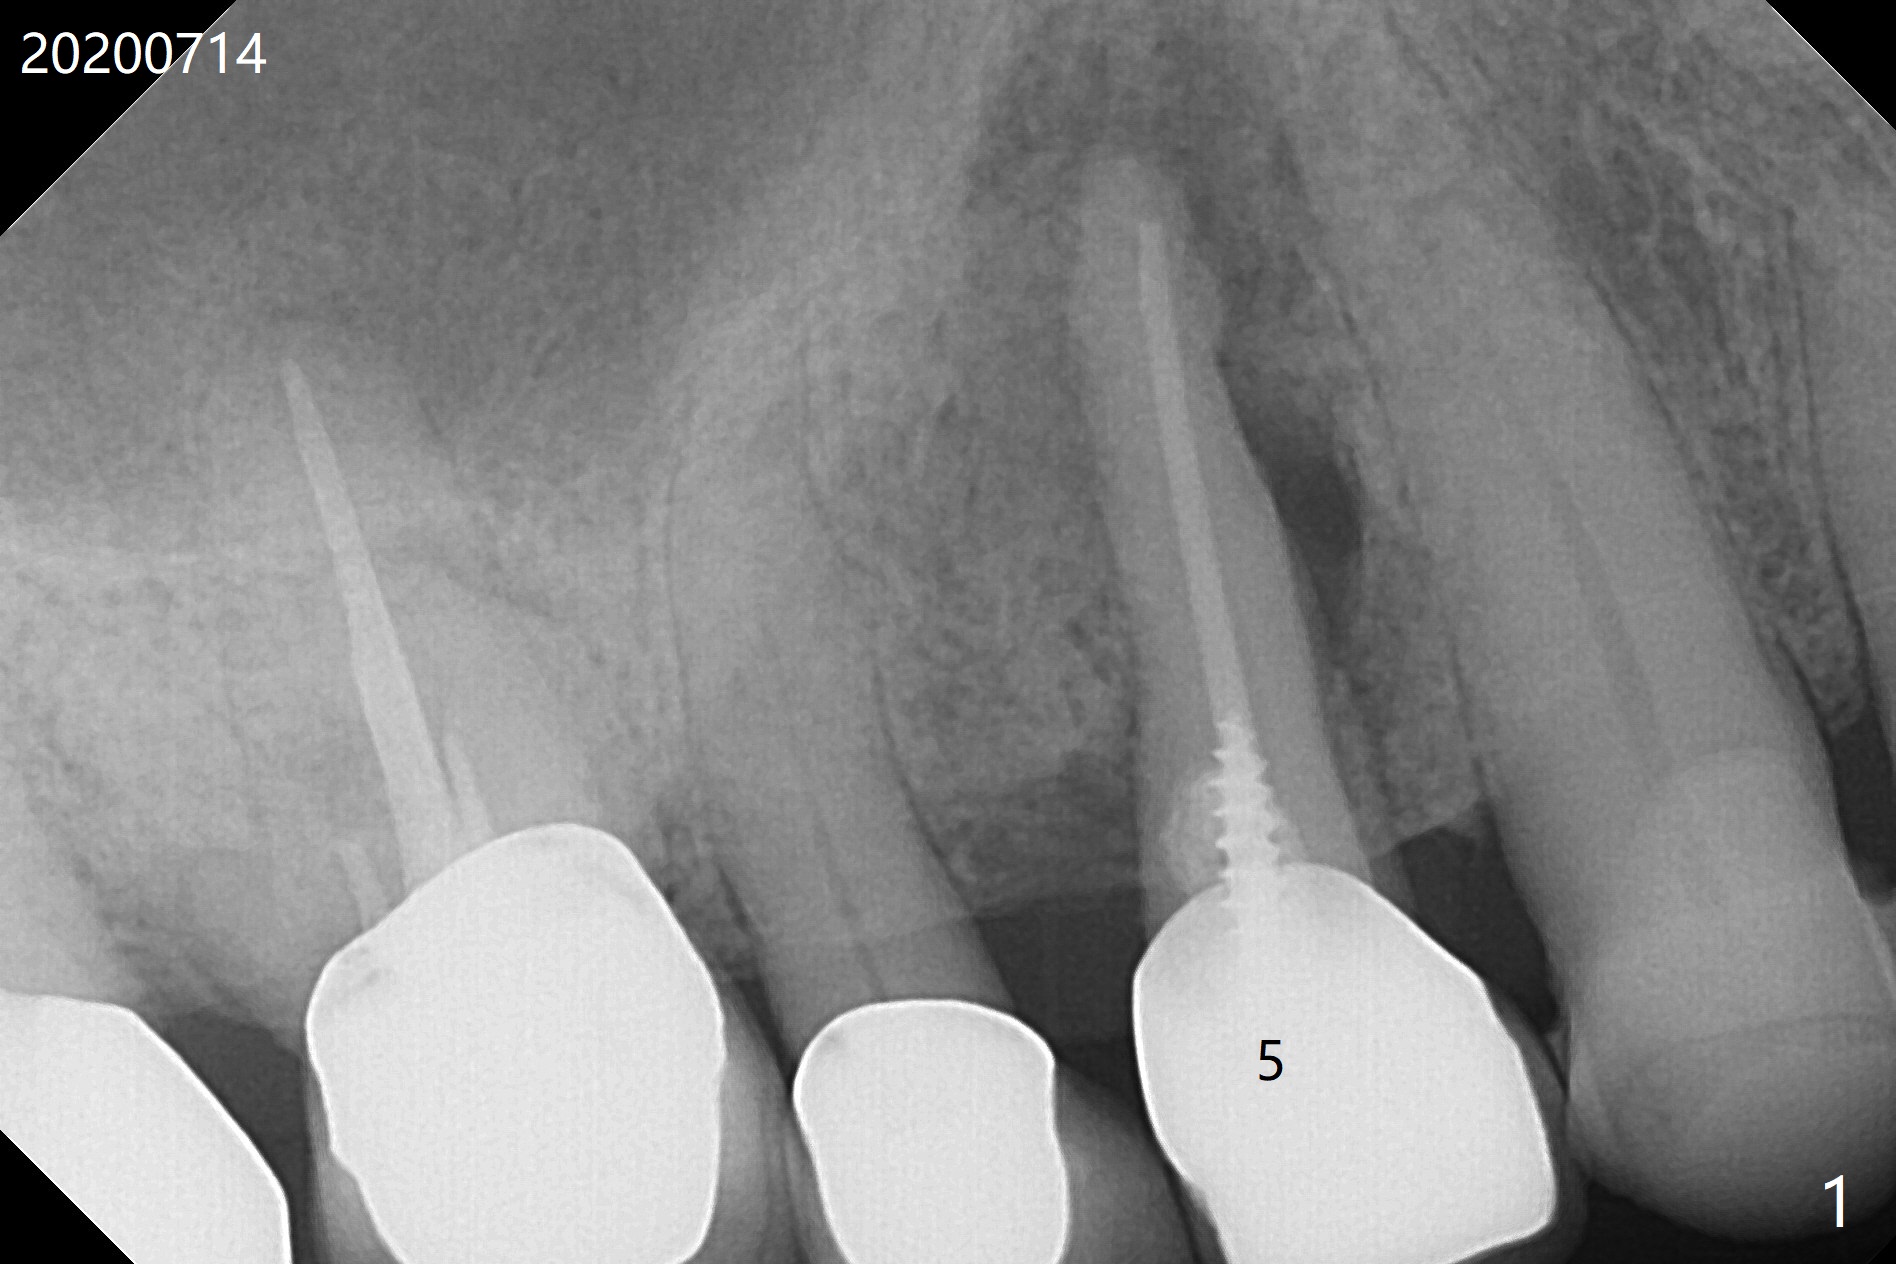

A 90-year-old man (bruxer) has porcelain fracture at #4. PA happens to reveal large PARL at #5 (Fig.1). CT taken a year ago shows missing buccal canal (Fig.2). Bone loss seems to be extensive (Fig.3,4 (root fracture?)). Access to the canal through PFM fails; the crown has to be removed (Fig.5). Fortunately the buccal canal is found and negotiable.